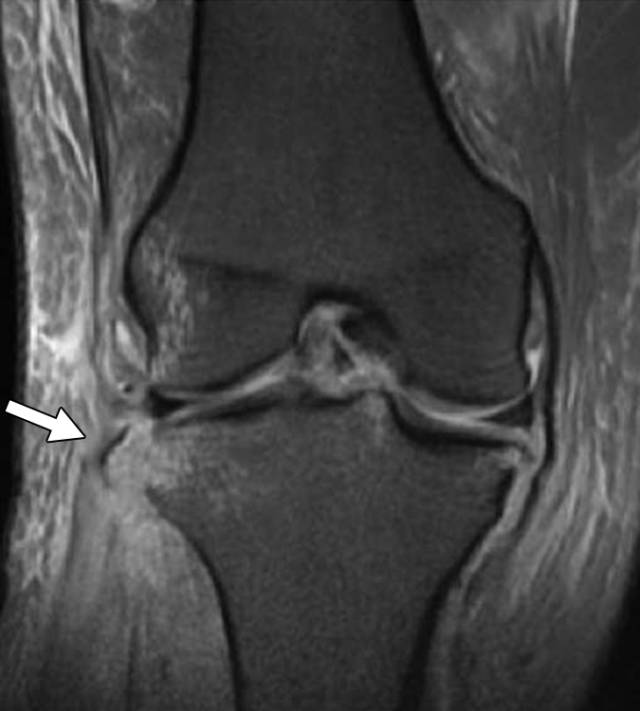

图7A、B、C-两名患者具有撕脱性骨折信号潜在损伤。A,32岁的踝关节受伤的男子在秋天受伤。侧面X线片显示最小移位后踝骨折(箭头),指示踝关节融合的破裂。B,30岁的男子汽车与行人碰撞后。冠状(B)和矢状(C)STIR MR图像显示在外侧胫骨坪(箭头,B)和全厚度前十字韧带撕裂处的急性Segond骨折。

另一个典型的例子是Segond断裂(图7B和7C)。这种骨折发生在外侧胫骨,似乎是侧膝关节囊撕裂的结果。已有许多研究显示Segond骨折与主要软组织损伤(包括前交叉韧带和半月板)的高度关联[29,30]。撕裂性骨折的其他频繁部位包括内侧和外侧股骨髁,胫骨的中间隆起,腓骨头,踝的内侧和外侧踝,远侧胫骨的前外侧边缘,距骨的背侧颈, 跟骨的前部过程,以及第二和第五跖骨的基部。当存在小的脉冲断裂片段时,放射科医生应确定通过哪种软组织结构附着于骨片段来考虑潜在的软组织分支。